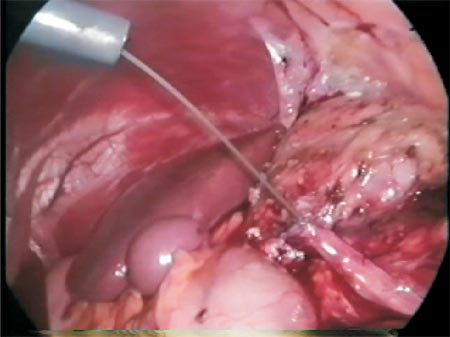

The Ureteral catheter is withdrawn and an antegrade Double J stent is passed over the guidewire (Photo 8). A pusher is used to insert the catheter into the renal pelvis (Photo 9). Then, always holding the Double J stent in the uteropelvic junction with an atraumatic forceps the vesical probe is withdrawn and afterwards the guidewire. Once again we pass the vesical probe in order to push any tip of the catheter that could be in the urethra. Next the anterior wall anastomosis is performed (Photo 10, 11, 12 and Figure 6). An abdomen X-ray is performed postoperatively to ensure the proper position of the Double J stent.

Photo 10 - Removal of the guidewire through the urethra of the patient after removing the vesical probe and the Double-J stent by twisting its tip.

Transperitoneal access was used; however, retroperitoneal access is also feasible. The intra-ureteral catheter facilitates its identification (Figure 2 and Photo 3). The ureter is traced cephalad toward the renal pelvis. NS (normal saline) 0,9% can also be injected through Levine catheter to distend even more the renal pelvis facilitating its identification (Figure 3 and 4). A 3.0 long straight needle could be passed percutaneously or not to lift the pelvis and therefore saving a trocar (Photo 4).

Photo 4 - 3.0 Nylon transfixing the skin to facilitate pelvis dissection